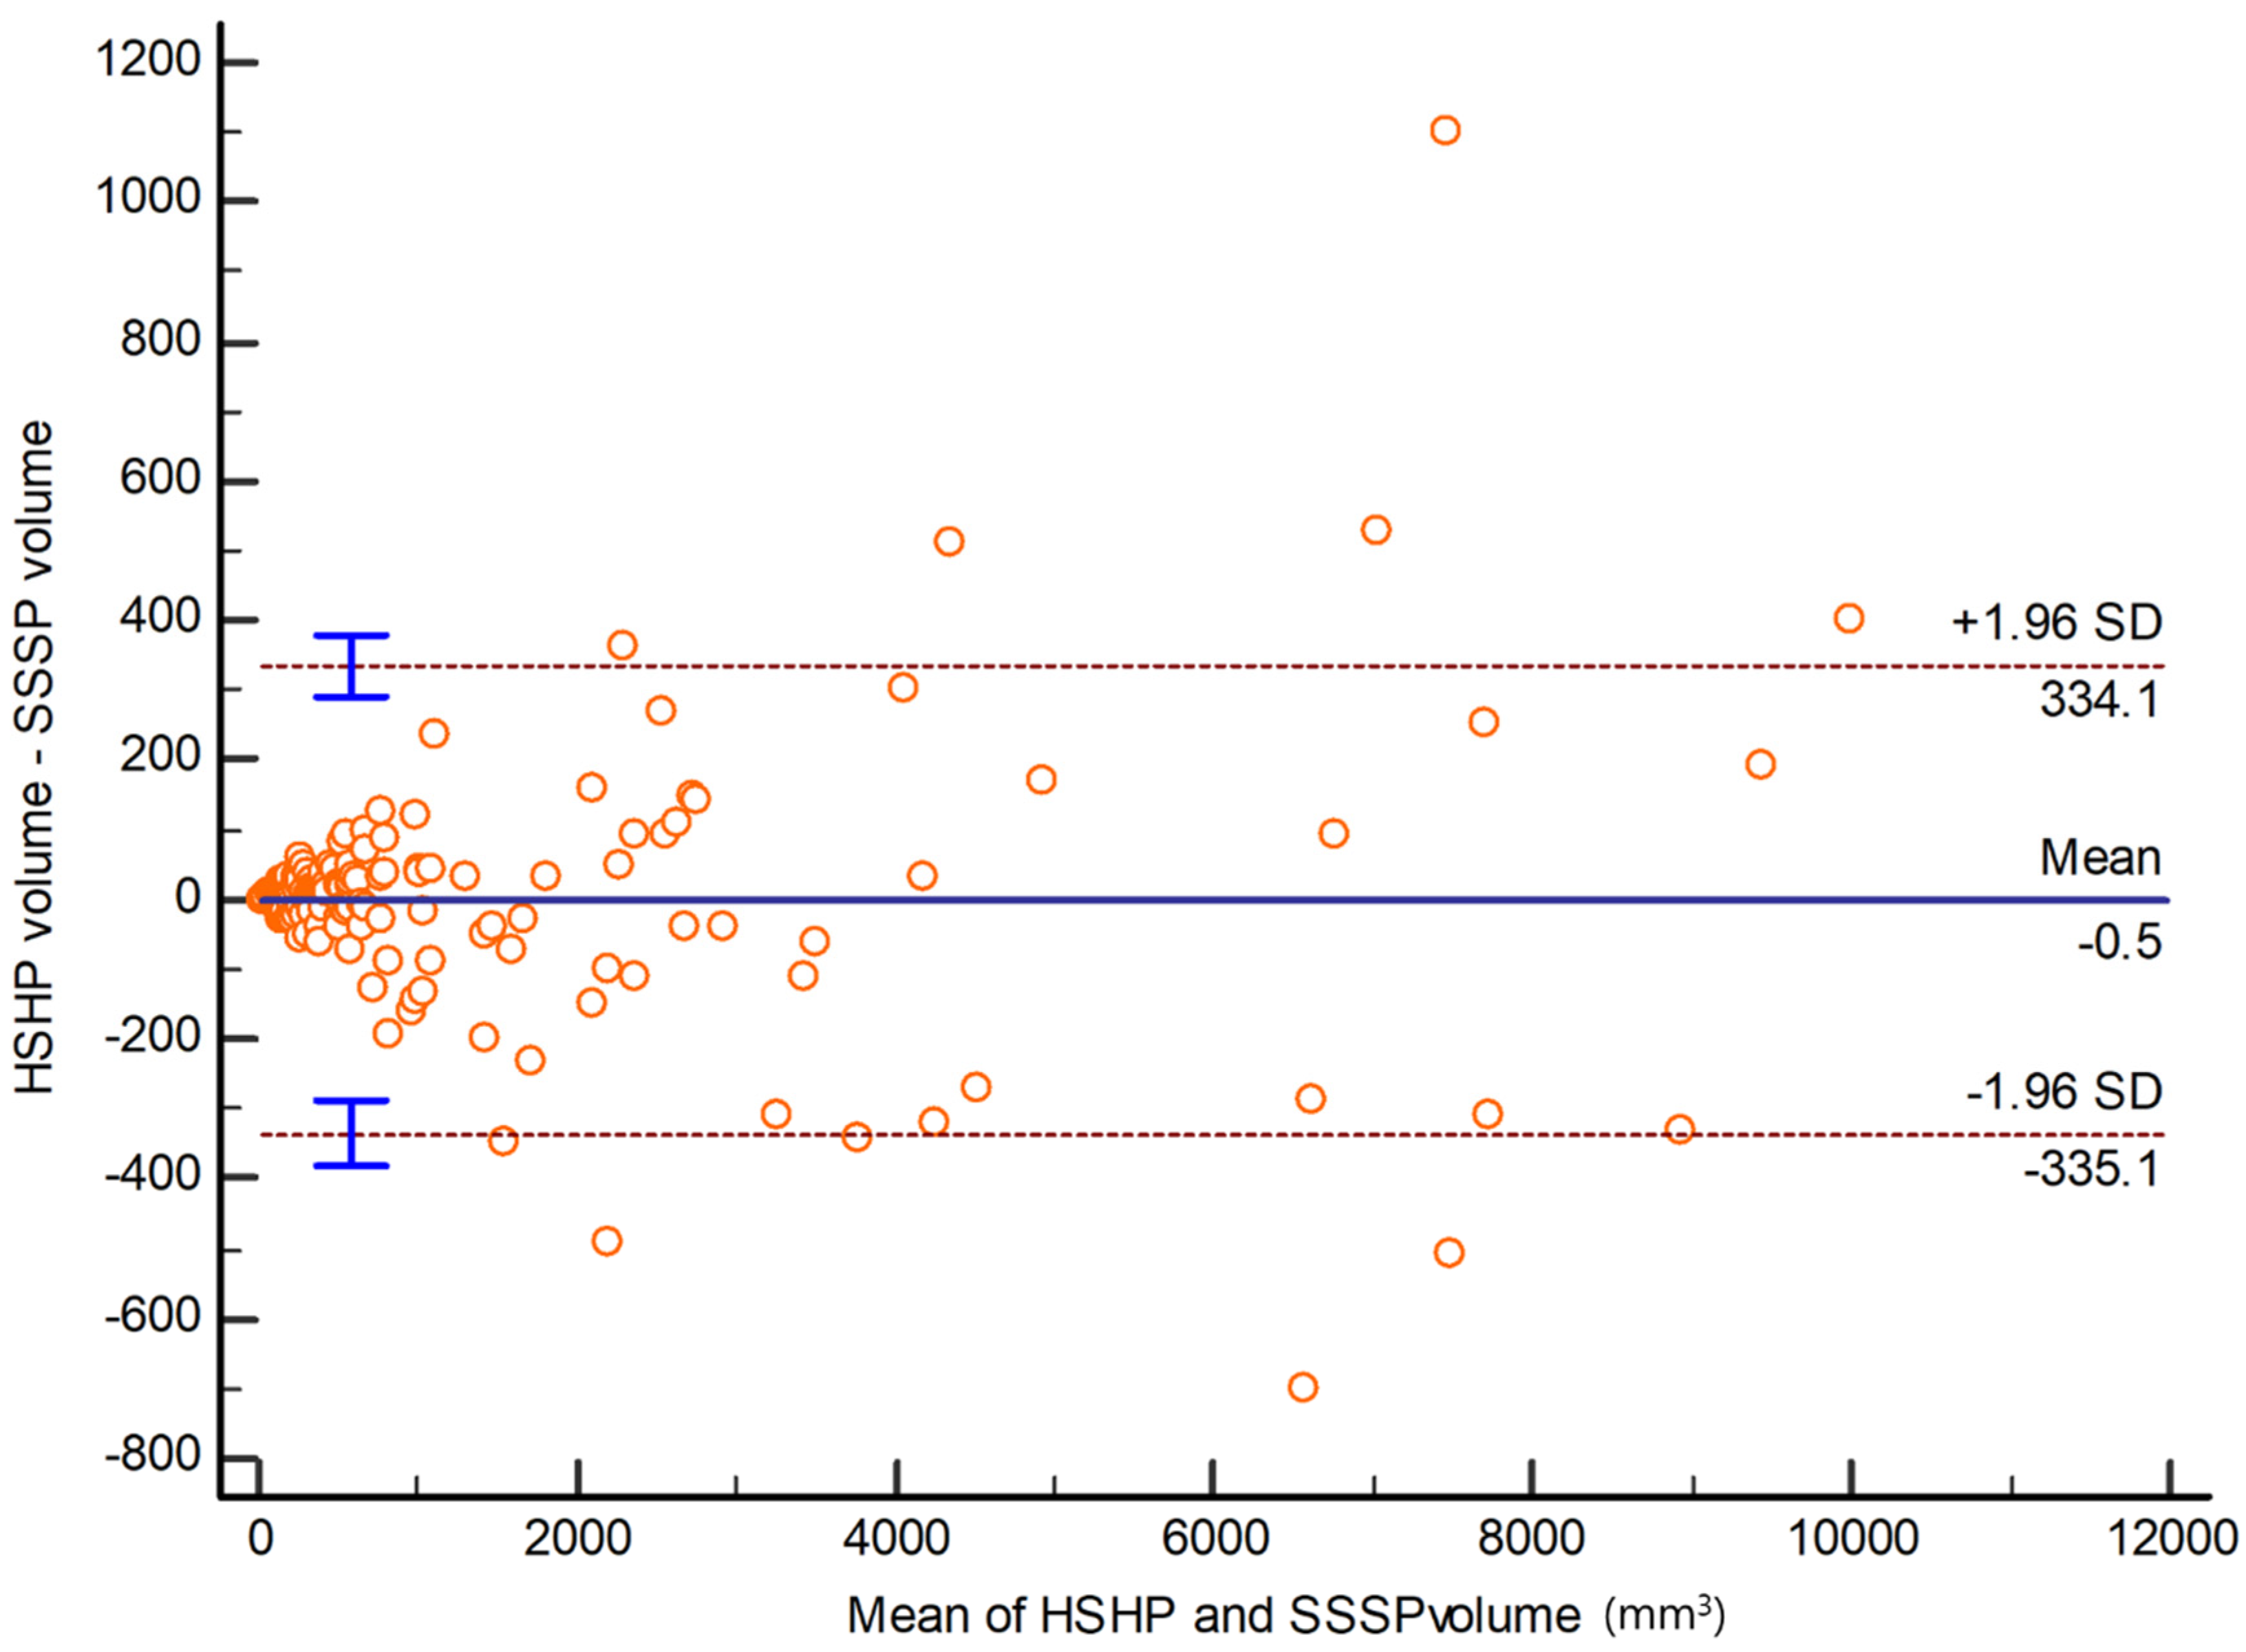

3.4. Subjective Image Quality Analysis between SSSP and HSHP

- Bland, J.M.; Altman, D.G. Statistical methods for assessing agreement between two methods of clinical measurement. Lancet 1986, 1, 307–310. [Google Scholar] [CrossRef]